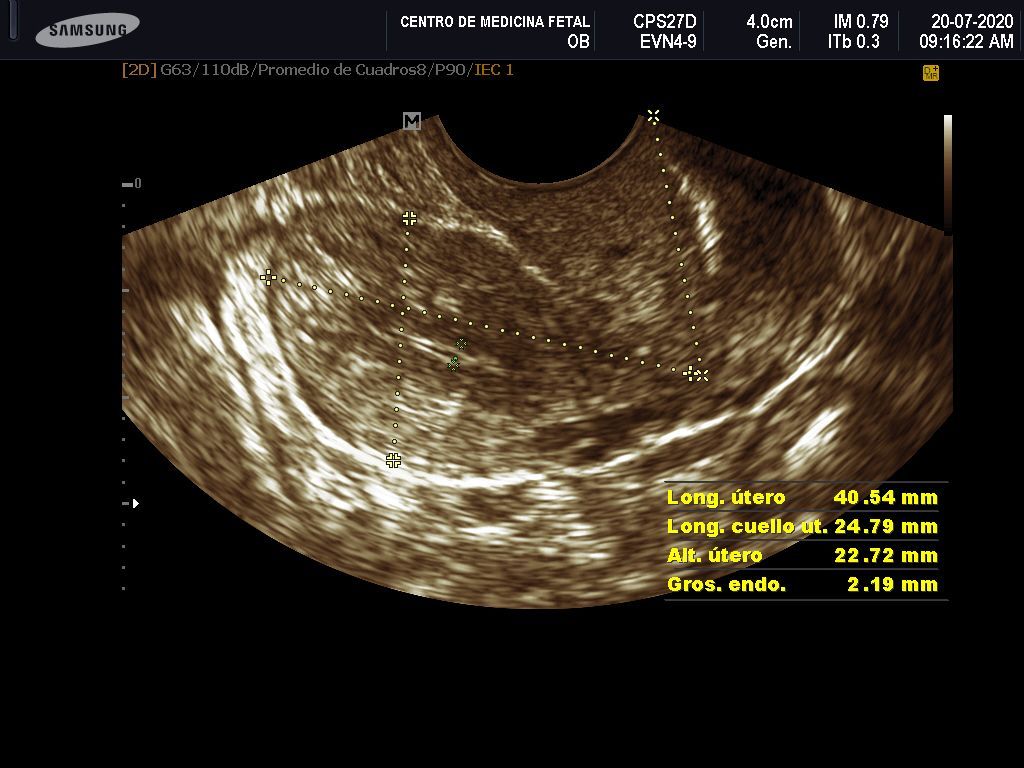

- Detección ecográfica transvaginal o pélvica y tratamiento de: Miomas, quistes de ovario, endometriosis, malformaciones uterinas